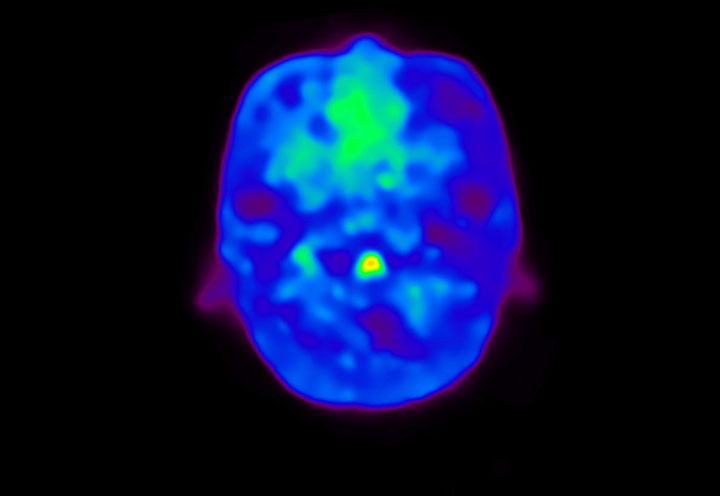

Head / Case4 : Amyloid

Axial

Courtesy : Kindai University Hospital

- Imaging protocol

- Injected dose: 3.21 MBq/kg, 18F-Flutemetamol

- Uptake time: 100 minutes

- Scan time: 20 minutes